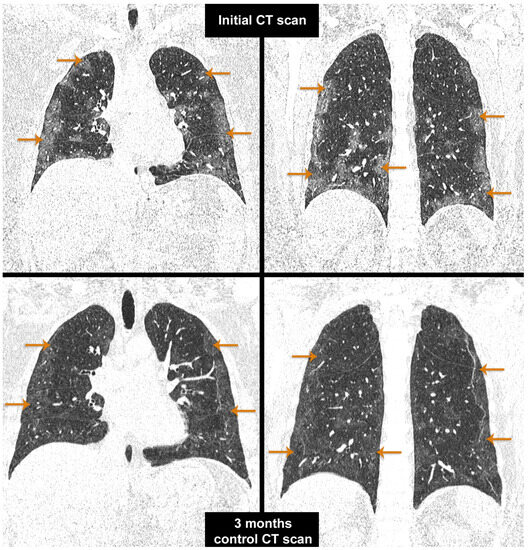

3.7. Evaluation of the Patients with NIMV

3.8. Evaluation of the Patients with IMV